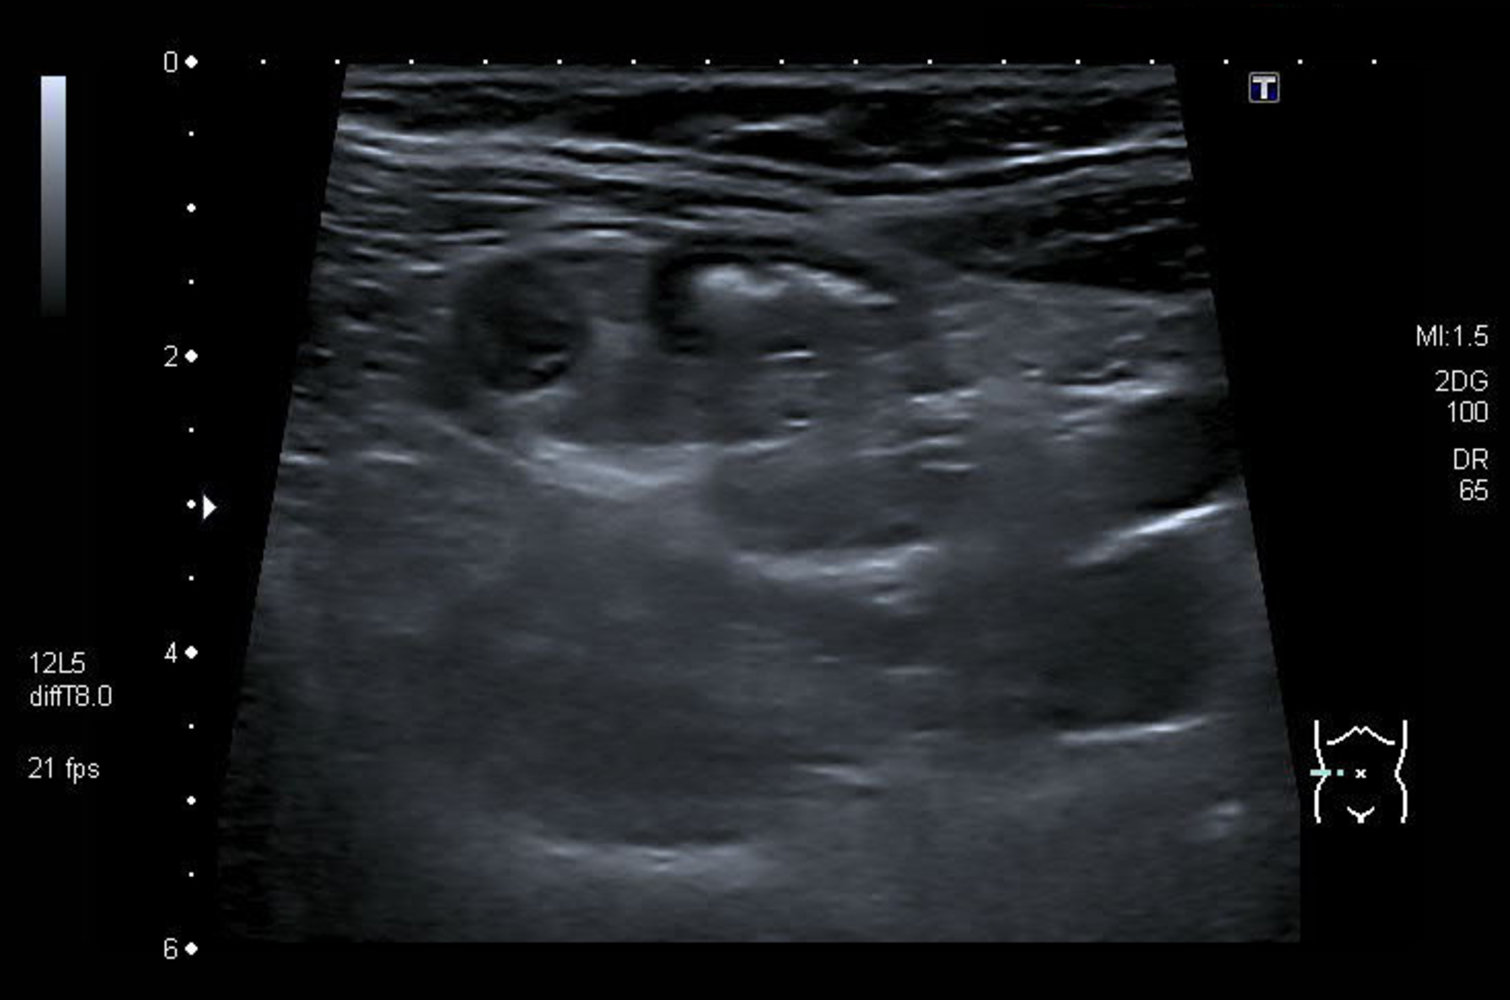

Abdominal ultrasound

Many institutions prefer ultrasound as the initial imaging modality, reserving CT scans for inconclusive ultrasound findings. [11][29]

Supportive findings [32]

- Distended appendix (diameter > 6 mm)

- Noncompressible, aperistaltic, distended appendix

- Target sign: concentric rings of hypo- and hyperechogenicity in the axial/transverse section of the appendix

- Possible appendiceal fecalith: focal hyperechogenicity with posterior acoustic shadowing

While abdominal ultrasound can confirm the diagnosis of acute appendicitis, normal ultrasound findings do not reliably rule out appendicitis. [10]